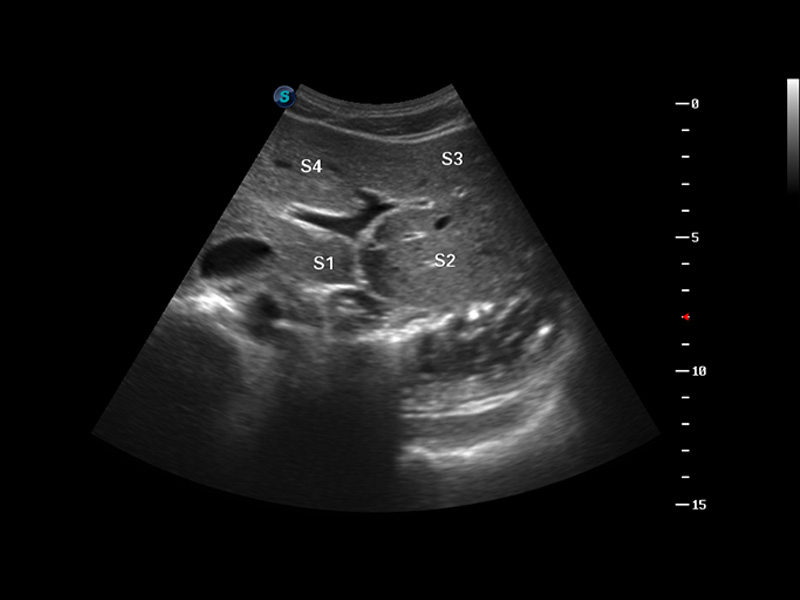

S8 EXP便携式彩色多普勒超声诊断仪是银河集团官网研发的高端全身应用型便携彩超。高通道的VIS平台融合可视化(Visual)、智能化(Intelligent)和人性化(Smart)的特点,配以银河集团官网自主研发生产的探头大家族,使您能够快速、准确的获得病人信息,提高工作效率的同时减轻疲劳。

成像技术

μ-Scan微米成像

谐波成像